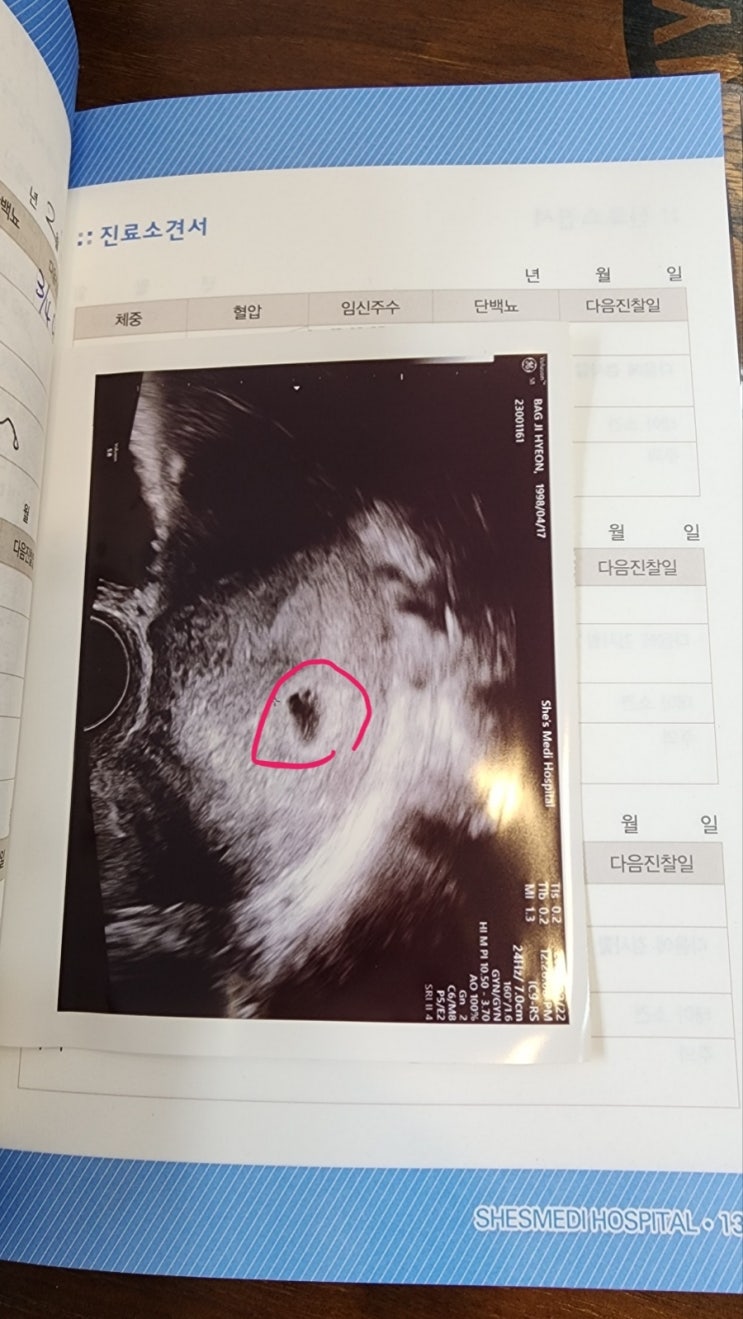

로라의 성별은...?! 임신 초기(9주~12주) 일기

3월 19일 집에가서 밥먹고 아빠한테 과일깎아달라했다 기대하는 표정 제법 욱겨... 친정엄마 밥은 입덧이 ...